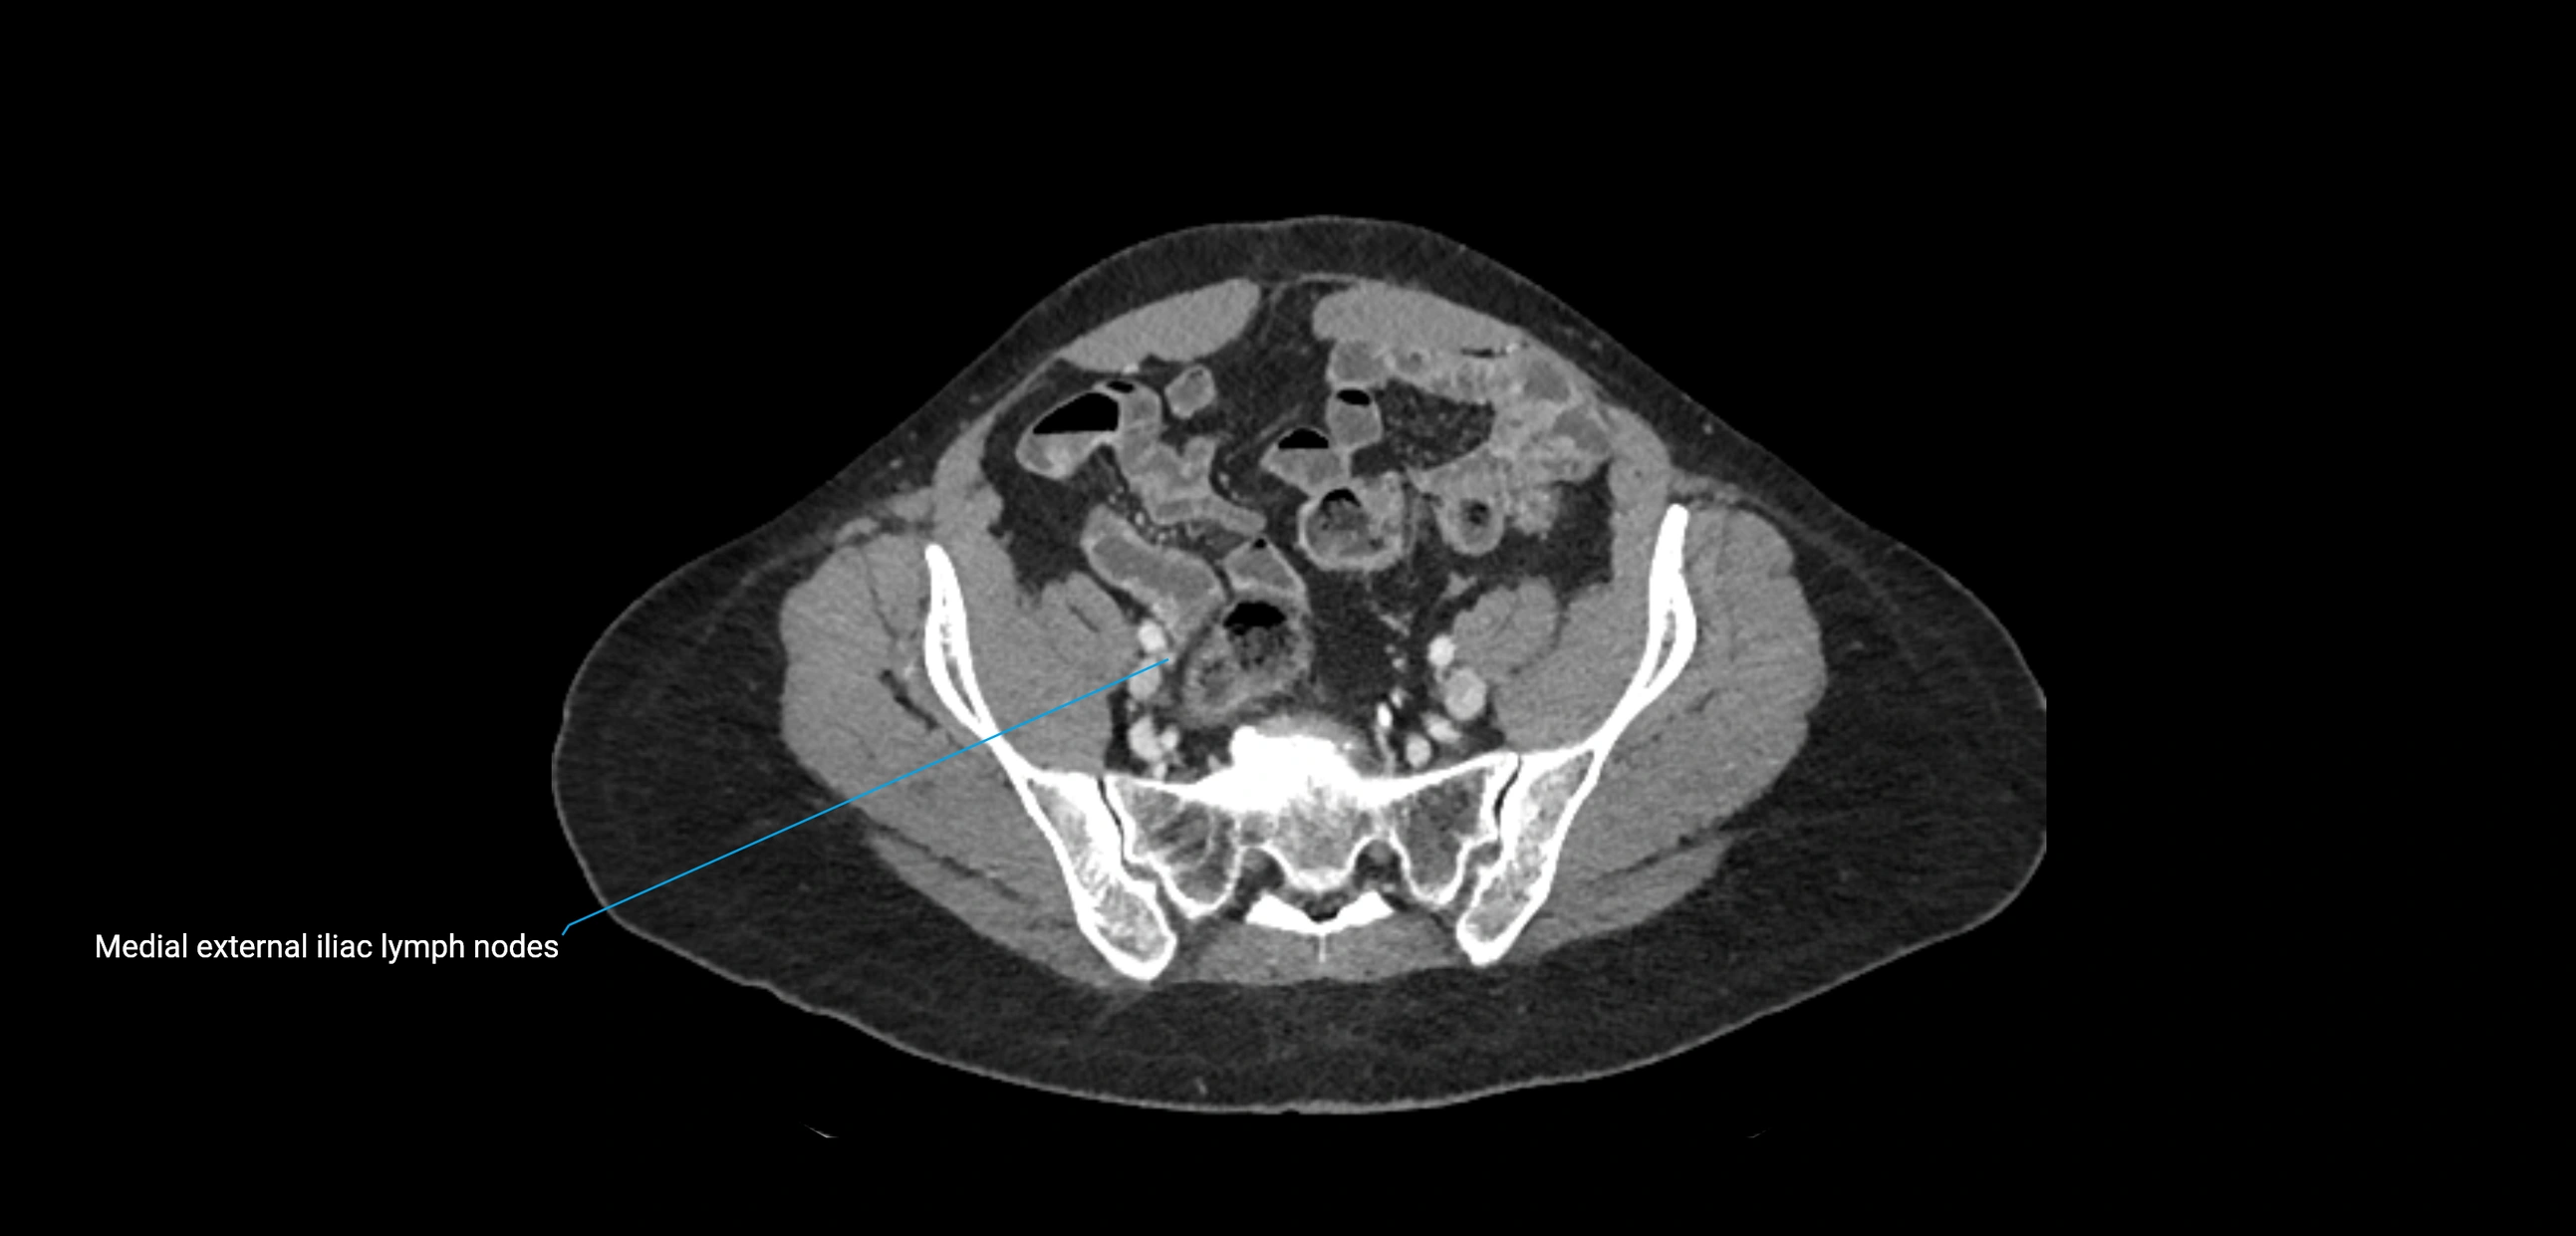

CT Appearance

CT Post-Contrast:

• Normal nodes enhance homogeneously

• Malignant nodes may show heterogeneous enhancement, central necrosis, or conglomerate formation

• Size >1 cm short axis is suspicious, though morphology and distribution are equally important

CT Venography (CTV):

• Demonstrates nodal encasement or compression of adjacent vessels (aorta, IVC, renal veins)

• Useful in staging testicular and ovarian malignancies

• Provides 3D reconstructions for retroperitoneal lymph node dissection planning